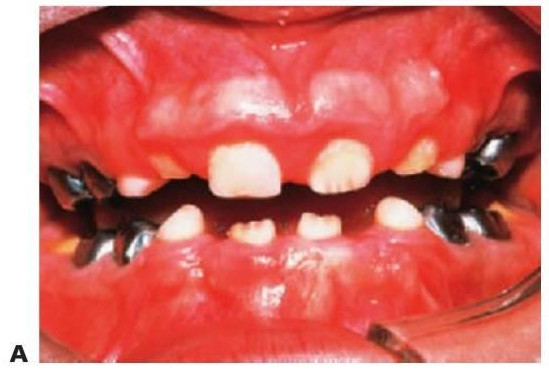

Hipodoncia, oligodoncia y anodoncia son los términos que designan los diferentes grados de progresión de la ausencia de dientes, si bien el término hipodoncia es el más utilizado debido a que se refiere a un número indeterminado de dientes ausentes (fig. 9.1 A). La oligodoncia designa la ausencia de seis dientes o más, y la anodoncia la ausencia completa de dientes. Todos estos casos se producen debido a un fallo en el desarrollo. El término «dientes ausentes congénitamente» no puede aplicarse a la dentición permanente, ya que estos dientes comienzan su desarrollo después del nacimiento, y tampoco a la dentición temporal ya que esa ausencia dental no puede determinarse de forma clínica en el momento de nacer; asimismo, el término «anodoncia parcial» carece de sentido. Sucede con frecuencia que los grados de hipodoncia aparezcan de manera esporádica o bien tengan un componente hereditario. Cuando a un individuo le faltan muchos dientes se debe estudiar a otros miembros de la familia afectados.

- Varios dientes ausentes (fig. 9.1 B).

Los dientes son pequeños y cónicos y a menudo presentan un gran diastema anterior (fig. 9.3). Sus manifestaciones pueden limitarse a un solo diente ausente o a un incisivo lateral en clavija (v. hipótesis de Lyon, más adelante) y las mujeres heterocigóticas suelen ser diagnosticadas gracias a este tipo de dentición.

Tratamiento

El objetivo del tratamiento es proporcionar una función adecuada, mantener la dimensión vertical y restaurar el aspecto estético. La mejor opción desde el punto de vista de las consideraciones sociales es el inicio del tratamiento a los 2-3 años de edad. Sucede a menudo que los padres pretendan con ahínco «normalizar» el aspecto del niño. Un primer paso suele ser la colocación de restauraciones de composite para enmascarar el aspecto «similar a un colmillo» del diente anterior caniniforme (fig. 9.3A). Más adelante se efectuará la provisión de prótesis para que sufra menos burlas, sobre todo en el momento en que el niño empieza a ir a la escuela. La prótesis puede prepararse tan pronto como al niño se le puedan tomar impresiones, pero la realidad es que el primer juego de prótesis suele llevarse en el bolsillo y a medida que el niño crece se desarrolla el deseo de tener un aspecto más normal. Gracias a una incentivación y refuerzo positivo del niño, la mayoría de los niños llevarán puestas sus prótesis.